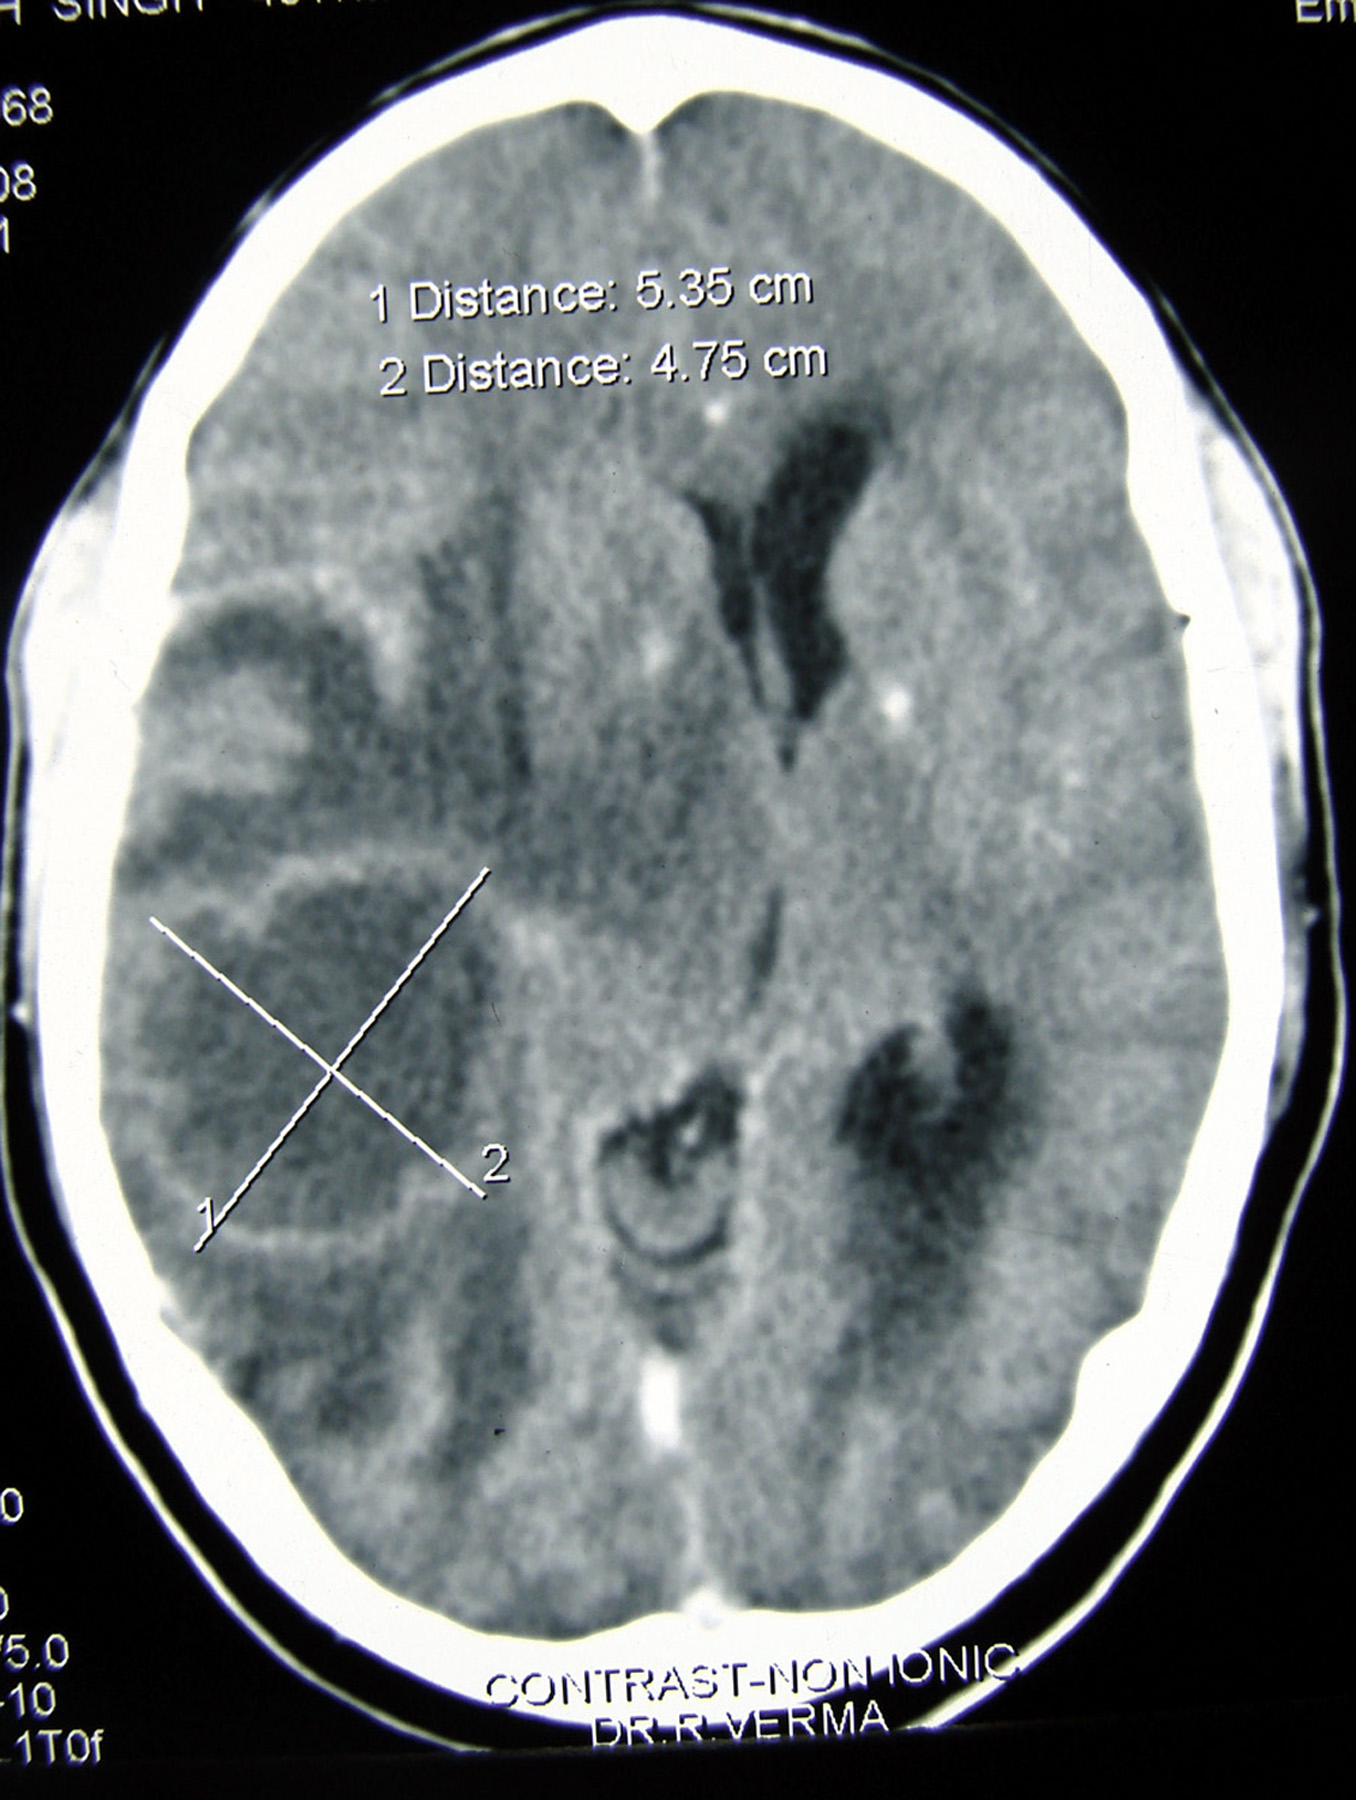

Spread of squamous cell carcinoma (SCC) commonly occurs vialocal lymphatic channels. Owing to scanty lymphatic drainage and vascular supply, SCC arising from the glottis rarely metastasizes. A 39-year-old male, operated for SCC of the glottis, presented 13 months later with complaints of headache. Computed tomography revealed a single ring-enhancing lesion in the right temporo-parietal region of the brain, suggestive of brain abscess. However, histopathological examination of the excised brain lesion showed metastasis of moderately differentiated SCC. Here, we report a rarecase of distant hematogenous brain metastasis of SCC of the glottis.